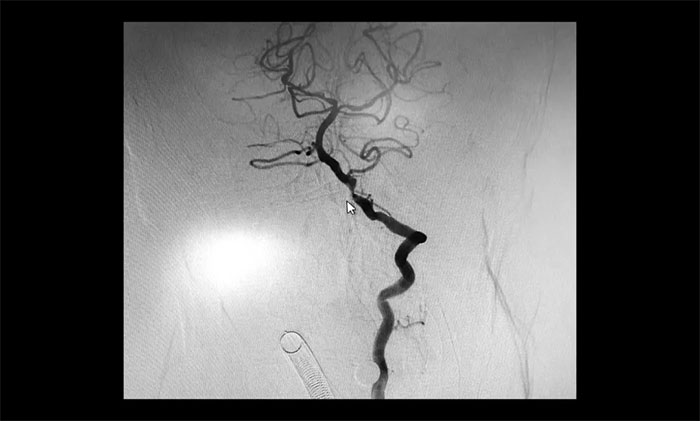

在明確告知分期手術(shù)方案,并取得患者家屬同意后,5月21日,于耀宇主任和團(tuán)隊(duì)醫(yī)生在全麻下為曹老伯先行腦血管造影術(shù)+左側(cè)頸內(nèi)動(dòng)脈支架經(jīng)皮置入術(shù),術(shù)后給予預(yù)防感染、護(hù)胃、補(bǔ)液等對(duì)癥治療。

▲ 術(shù)后,左側(cè)頸內(nèi)動(dòng)脈狹窄明顯改善